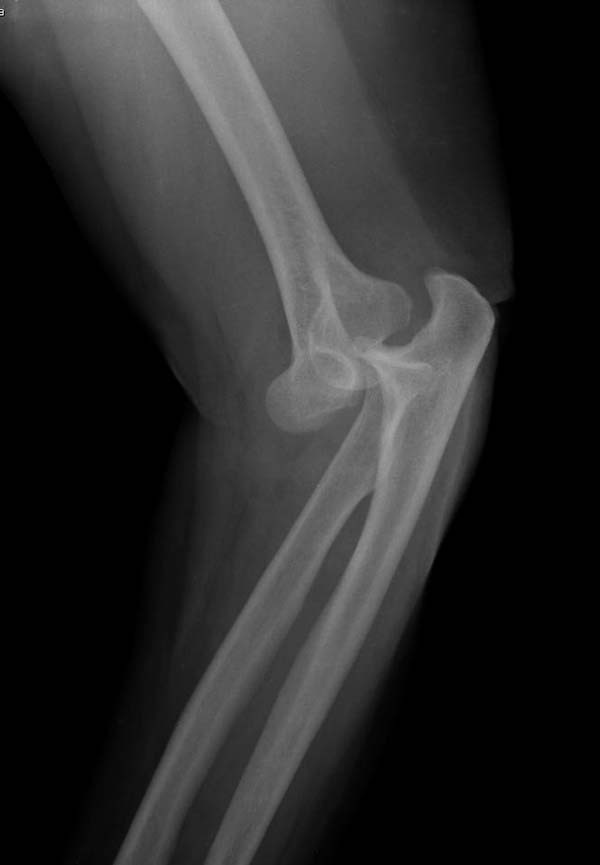

Снимки: 1-2 вывих, 4-5 вторичное смещение в гипсе, реконструкция

латеральной связки и капсулы 13-14, повторный вывих после реконструкции,

Вложение не в текстовом формате было извлечено…

Имя     : 2 Elbow dislocation injury.jpg

Тип     : image/jpeg

Размер  : 48147 байтов

Описание: отсутствует

Url     : http://weborto.net:8080/pipermail/ortho/attachments/20131212/4b05a6a3/attachment-0007.jpg